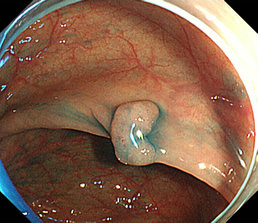

見つかったポリープ

ポリープに色素を吹きかけた状態

粘膜下層に生理食塩水を注入し、盛り上げた状態

高周波電流で粘膜下切除を行った状態

切除後クリップにて止血胃瘻造設術